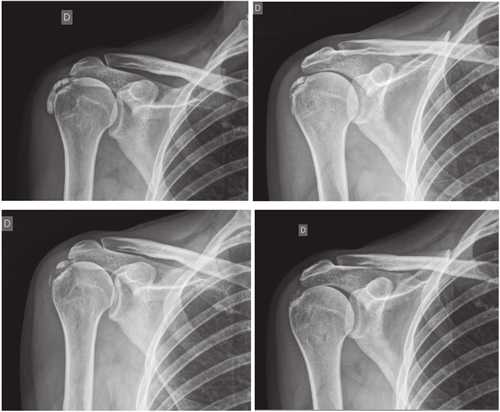

El número promedio de sesiones en nuestra serie fue de 20. El criterio para continuar o suspender el tratamiento fue la evolución radiológica y clínica (Figuras 4 y 5). Las intervenciones se realizaron hasta un máximo de 40 sesiones. Perrón trató a sus pacientes por 9 sesiones (3 sesiones semanales por 3 semanas) (14). Leduc trató con 10 sesiones (3 por semana las dos primeras semanas; y luego una semanal por 4 semanas) (15). Rioja-Toro trató a sus pacientes por 40 sesiones (5 veces por semana) y los evaluó a las 20 y a las 40 sesiones (3). Chico-Álvarez trató a sus pacientes entre 15 y 30 sesiones dependiendo de la evolución radiológica (5 veces por semana) (1).

Fig. 5. Paciente mujer de 44 años, con tendinitis calcificante de supraespinoso izquierdo, de tipo resortivo, quien tras 20 sesiones de iontoforesis disminuyó el dolor medido por EVA de 10/10 a 4/10, y la calcificación de 22 mm a 0 mm (desaparición completa).